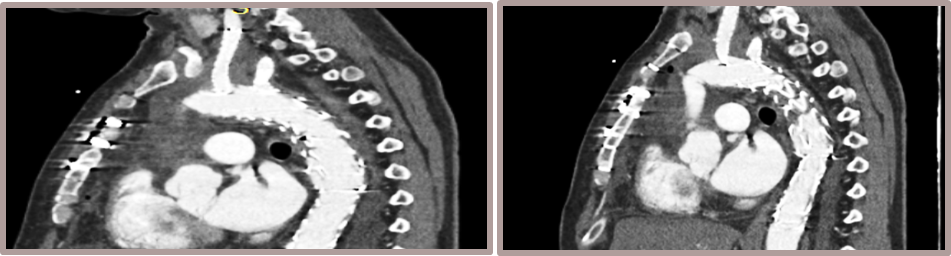

夹层动脉瘤CTA:逆撕A型主动脉夹层,升主动脉及无名动脉见夹层累及,左颈总及左锁骨下动脉烟囱支架。

术前影像

术后影像

术后CTA